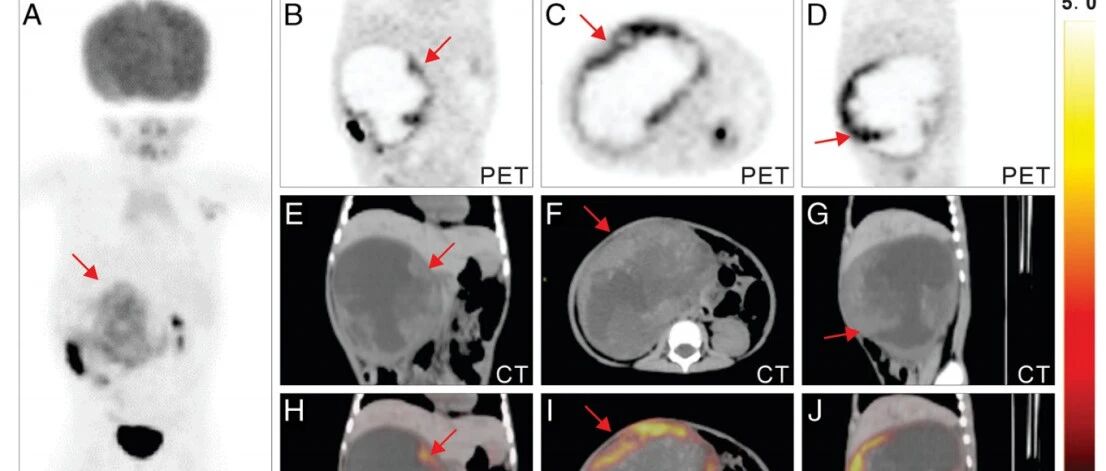

癌症治疗新纪元:靶向FAP的“诊疗一体化”